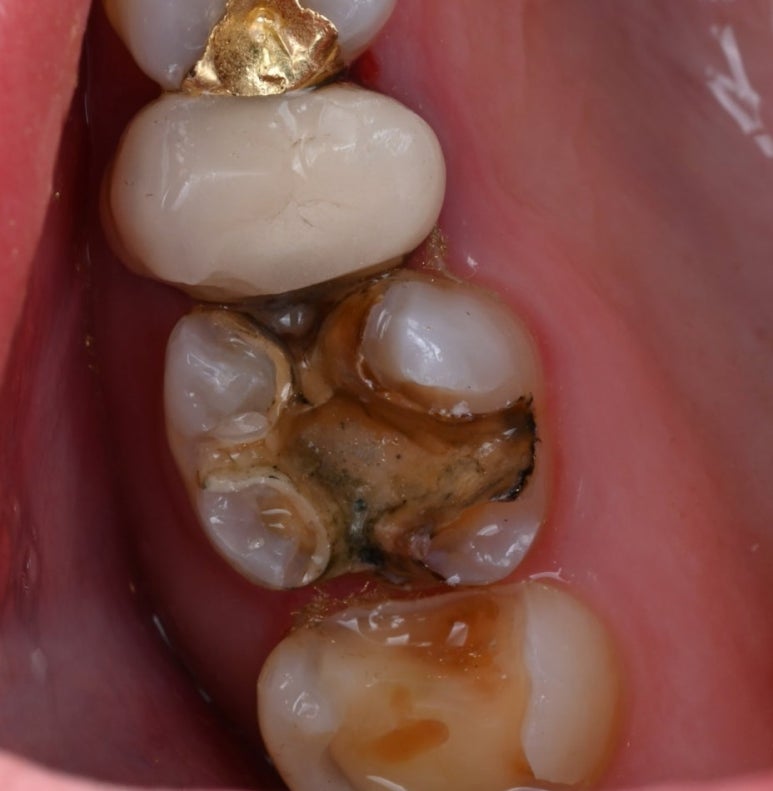

25.11.11 #17 치아의 금 인레이가 탈락하고 충치가 발생한 모습.

25.11.11 앞쪽 어금니(#16) 금 인레이 하방에서 발견된 충치

문제가 된 큰 어금니를 치료하던 중,

바로 앞쪽 어금니(#16)의 상태도

심상치 않음을 발견했습니다.

이 치아 역시 금 인레이가 되어 있었는데,

틈새로 비쳐 보이는 내부가

이미 충치로 오염되어 있었습니다.